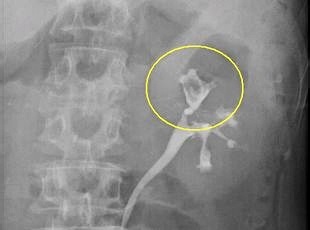

当院では腹部超音波検査、CT検査、MRI検査、逆行性腎盂・尿管・膀胱造影検査、腎盂尿管鏡検査、膀胱鏡検査などを駆使し、無症状の尿路上皮がんの早期発見に努めています。

腎盂・尿管がんに対する治療は、手術療法が主体です。手術はがんが発生した片側の腎臓、尿管および膀胱壁の一部も含めた腎尿管全摘除術、膀胱部分切除術を施行するのが一般的です。当院では腹腔鏡下腎尿管全摘除術を行います。